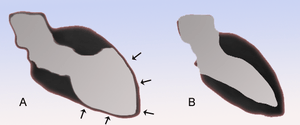

A depicts the left ventricular dilation that occurs in Takotsubo cardiomyopathy compared to a normal heart in B.

- Bulging out of LV apex with preserved function of the base looks like an octopus pot or "tako tsubo" in Japanese

LV apical ballooning during systole

- Apical Ballooning on US